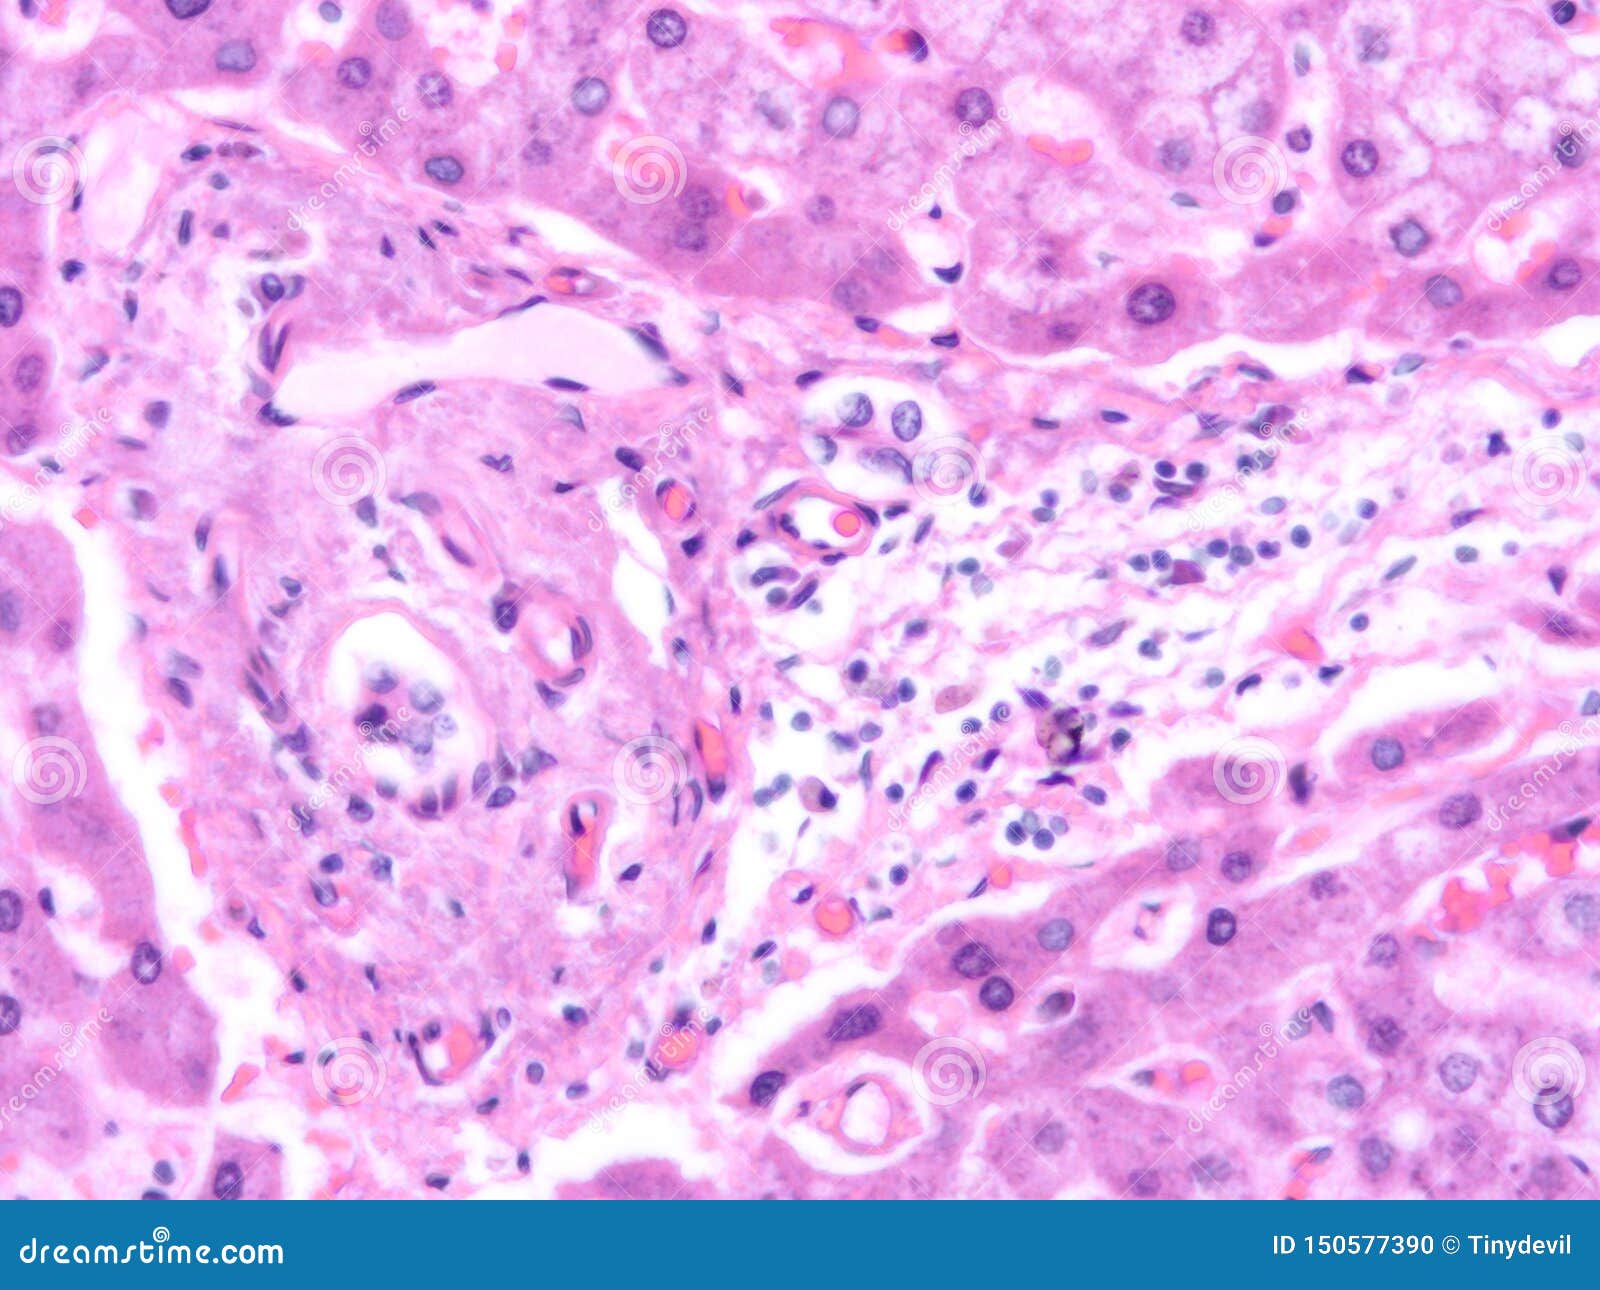

Histology of Human Liver Tissue Stock Photo Image of medical, health 150577390 Liver Tissue Histology The liver, the largest organ in the body, plays a major role in the uptake, storage and distribution of nutrients. A lobule is roughly hexagonal in shape, with portal triads at. Parenchyma, which is represented by hepatocytes; Individual chapters in this richly illustrated atlas cover the wide gamut of liver disease, including types of liver injury, viral hepatitis, fatty liver. Liver Tissue Histology.

From www.dreamstime.com